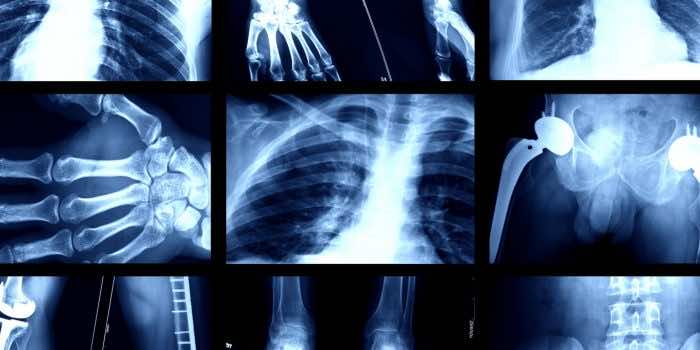

人工智能的深度学习模型现在能够从X射线射击中识别某人的种族。

“我们表明,可以培训标准的AI深度学习模型,以预测各种成像方式高性能的医学图像,这在外部验证条件下得到了维持。”

本文以先前的发现为基础,该发现表明,人工智能扫描X射线图像更有可能错过黑人疾病的迹象。

该系统可能正在发现黑色素的迹象,黑色素是赋予皮肤颜色的色素,科学尚不清楚。

研究人员写道:“我们的发现,即AI可以准确地预测自我报告的种族,即使是从损坏,裁剪和噪音的医学图像中,通常是在临床专家无法进行的,这会给所有模型部署中的所有模型部署带来巨大的风险。”